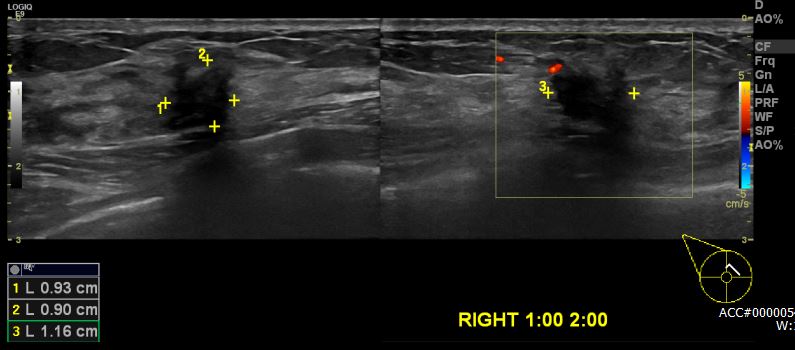

건강검진상 이상소견으로 내원하신 40대 여성분으로 본원 초음파상 우측 1시에서

2시 방향에 의심스러운 멍울 조직검사 시행하여 우측 침윤성 유관암 진단 되었습니다.